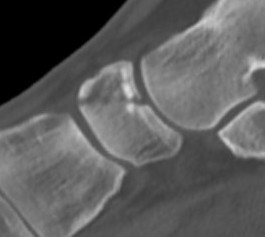

Acute, minimally displaced navicular fracture

Acute displaced navicular fracture